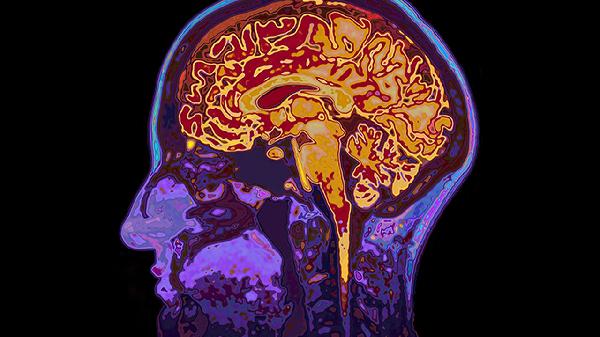

头颅CT是急诊首选检查,发病6小时后可显示低密度梗死灶。弥散加权核磁共振能在发病2小时内检测缺血区域,敏感度超过95%。血管造影可明确闭塞血管位置,CTA或MRA能无创评估脑血管狭窄程度。